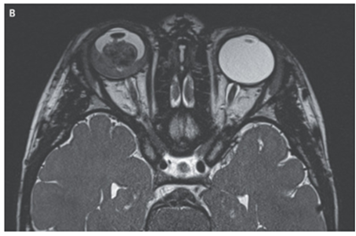

頭部MRIでは石灰化を伴う腫瘤と硝子体内播種が示唆され、また眼球外への進展を伴わない網膜および脈略膜浸潤が示された。